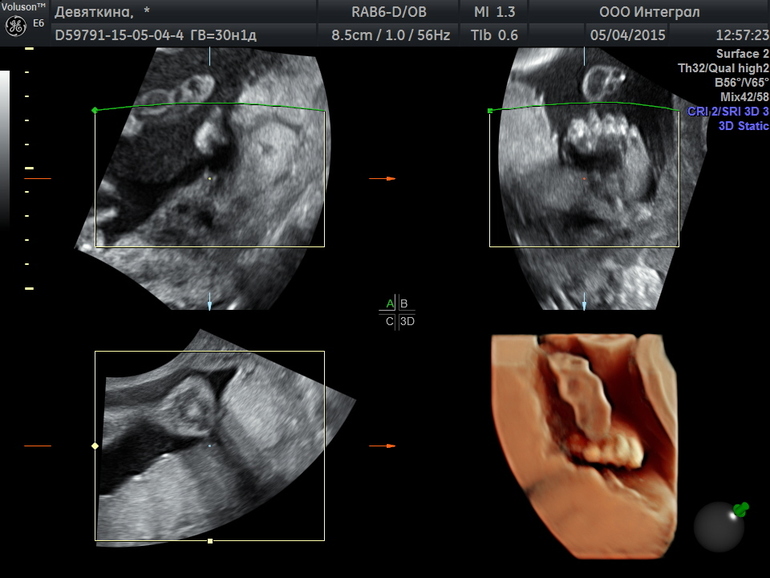

Малыш чувствует себя превосходно и уже весит 1557гр.

Посмотрели кровоток, сердечко, пупавину и многое другое все на высшем уровне))) Так что вывод, нашему сыночке комфортно)

Правда в день УЗИ он уселся в попное прилежание) А наследующий день лег поперек) живот у меня выпер в по бокам))))